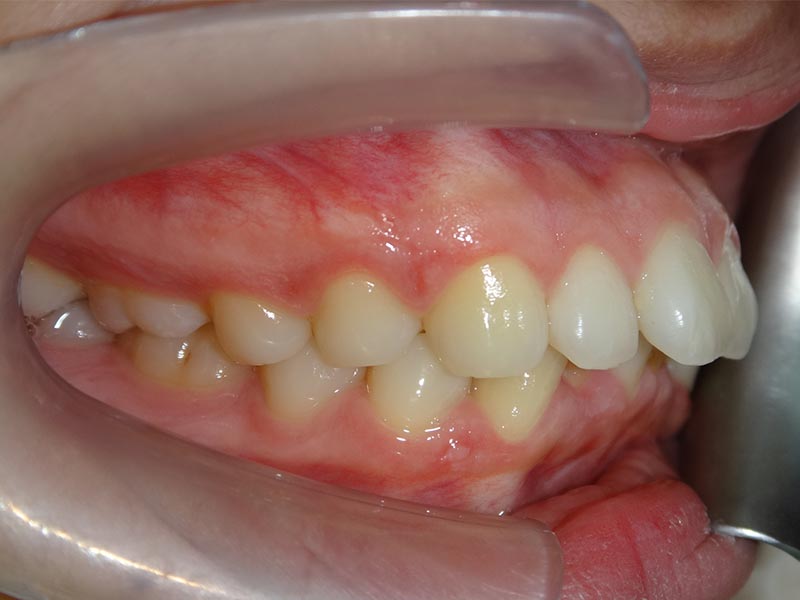

隱適美拔牙改臉型(二) 首頁 案例分享 齒顎矯正 隱適美拔牙改臉型(二) 拔牙改臉型案例 年紀:20 歲 女性 治療方式:隱適美隱形矯正 時間:29個月 主訴:外觀看起來比較暴,希望可以把牙齒排列整齊以及後縮 矯正前 矯正後 矯正前 矯正後 矯正前 矯正後 聲明:本所療程皆由專業醫生評估後,依照個人口腔狀況進行治療。因每位患者個別狀況不同,術後狀況也不盡相同,需親來本所由醫生評估。